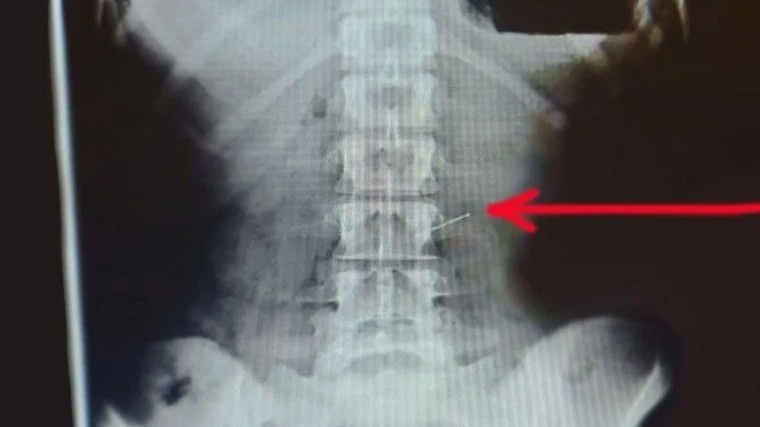

Рентгеновский снимок пострадавшей. Фото: Министерство здравоохранения Московской области

В Пушкине 30-летняя женщина проглотила булавку во время шитья, сообщают dni.ru со ссылкой на пресс-службу подмосковного Минздрава. По словам медиков, она для удобства держала в зубах несколько булавок, одну из которых случайно съела.

«Мы достали булавку при помощи эндоскопа. Нам потребовалось около часа, чтобы при помощи специального зажима для извлечения инородных тел „поймать“ злополучную булавку и достать, не повредив при этом желудок и стенки пищевода», — рассказал заведующий эндоскопическим отделением Московской областной больницы имени профессора Розанова Дмитрий Александровский.

Задачу по поискам инородного тела врачам осложнил завтрак, которым женщина полакомилась после того, как съела иглу. Пациентка поела сырников, а они, в свою очередь, затруднили обзор. Навредить могли и перемещения.